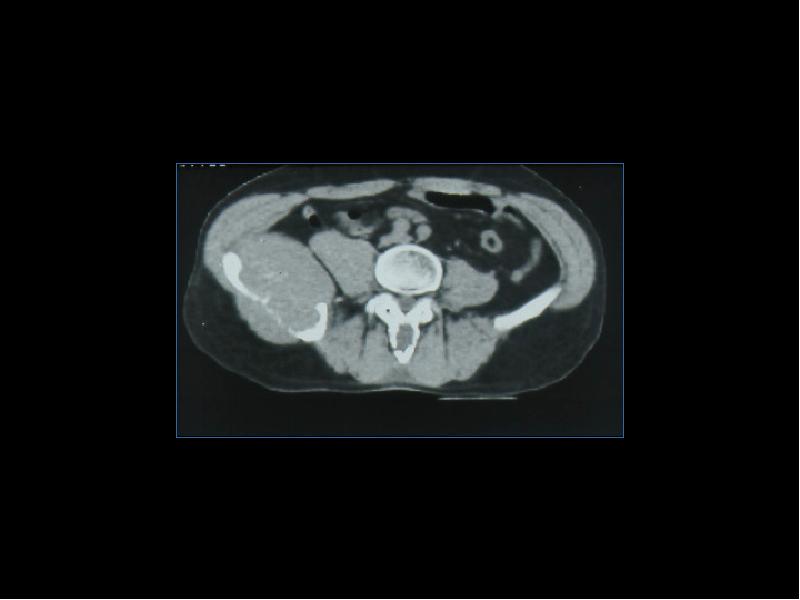

Лучевая диагностика доброкачественных